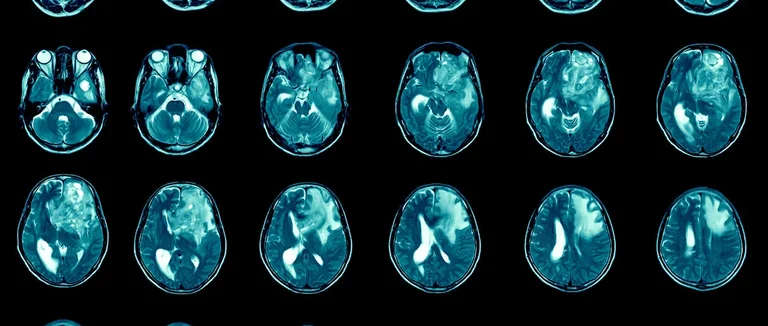

Plusieurs méthodes d'imagerie médicale aident à diagnostiquer les tumeurs cérébrales. Les scanners CT et l'IRM sont les plus utilisés.

Les scanners CT sont rapides et utiles en urgence. Ils détectent bien les hémorragies et les lésions cérébrales.

La tomodensitométrie, ou scanner CT, est une grande avancée en imagerie médicale. Elle combine rayons X et informatique pour montrer les détails internes du corps.

Principes de fonctionnement des scanners CT

Les scanners CT tournent un faisceau de rayons X autour du corps. Ils prennent des images de différents angles. Un ordinateur les assemble pour montrer une image transversale du corps.

Différence entre les rayons X standard et les scanners CT

Les rayons X standard donnent une image 2D. Mais les scanners CT montrent les structures internes en 3D. Cela aide beaucoup dans le diagnostic des tumeurs cérébrales.

Évolution de la technologie CT et précision améliorée

La technologie des scanners CT a beaucoup changé. Elle est maintenant plus précise et rapide. Les scanners modernes prennent des images en quelques secondes, ce qui améliore la qualité.

En conclusion, les scanners CT sont une méthode précise et rapide pour diagnostiquer. Ils aident beaucoup dans le soin des patients, y compris pour les tumeurs cérébrales. Leur évolution continue améliore les soins médicaux.

Les CT scans sont cruciaux pour diagnostiquer les tumeurs cérébrales. Ils sont très efficaces pour trouver différents types de tumeurs. Mais, ils ont aussi des limites.

Types de tumeurs cérébrales visibles sur un scanner CT

Les scanners CT peuvent repérer plusieurs types de tumeurs cérébrales. Ils sont bons pour les tumeurs grandes et celles avec des caractéristiques uniques comme des calcifications ou des hémorragies.

Les tumeurs visibles comprennent les gliomes, les méningiomes et les métastases cérébrales. Chaque type a des traits uniques que l'imagerie CT peut identifier.